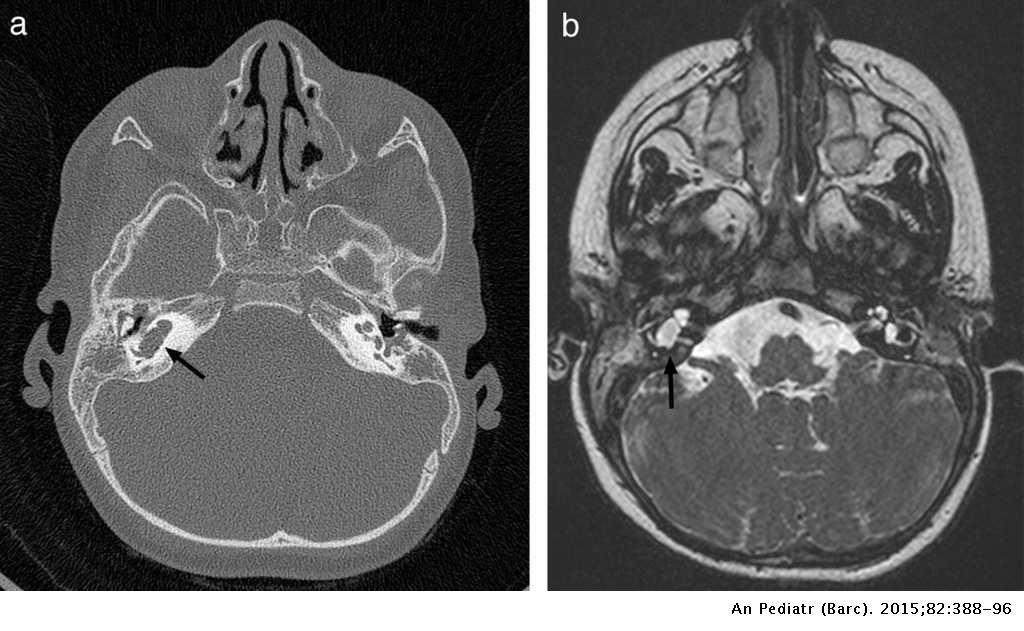

¿Cuáles son las complicaciones de la meningitis?

¿Cuál es el mejor estudio de imagen para las complicaciones de la meningitis?